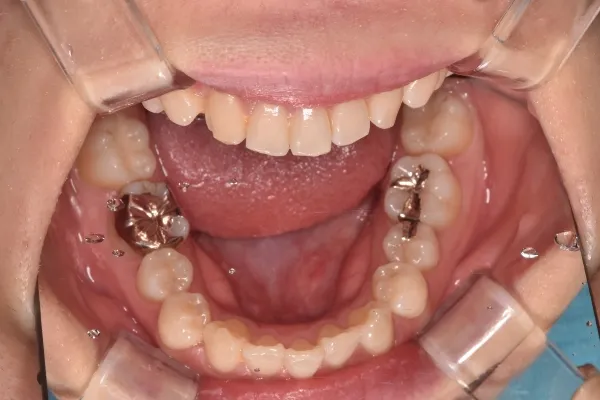

開咬

| 診断名・主訴 | 開咬 |

|---|---|

| 年齢・性別 | 18歳・男性 |

| 治療期間・回数 | 1年 12回 |

| 治療に用いた主な装置 | ロール付きリンガルアーチ |

| 抜歯部位 | なし |

| 治療費 | 70万円(税抜) |

| リスク・副作用 | 装置による違和感・疼痛・歯肉退縮・歯根吸収・虫歯のリスクなど |

治療前

治療中